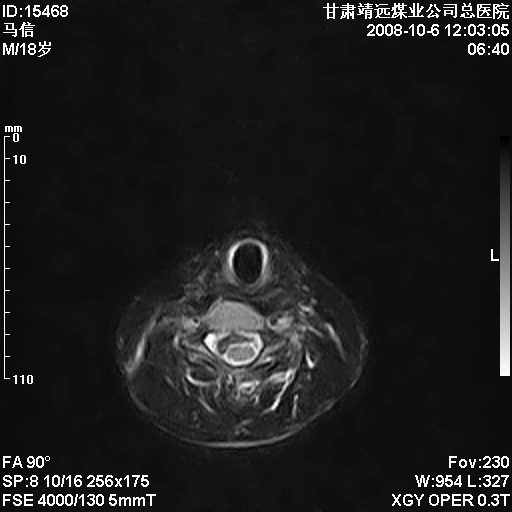

标题: MRI1827:颈椎内异常信号,是不是占位。

患者18岁,学生,在玩耍中受伤来检查,患者喜欢打篮球。颈椎内异常信号影,我们考虑占位,但是不像占位,又考虑硬膜囊的增厚,大家关建看颈椎椎管内的那个异常占位信号

腰椎的改变是不是正常发育的改变,还是打篮球的长期慢性损伤。

后纵韧带增厚,颈2/3、3/4、4/5、5/6椎间盘变性、突出;椎体有旋转,提示椎小关节有问题;腰椎间盘变性,许莫氏结节。

后纵韧带增厚,颈2/3、3/4、4/5、5/6椎间盘变性、突出;椎体有旋转,提示椎小关节有问题。腰椎诸椎体终板骨骺炎可能性大!支持!